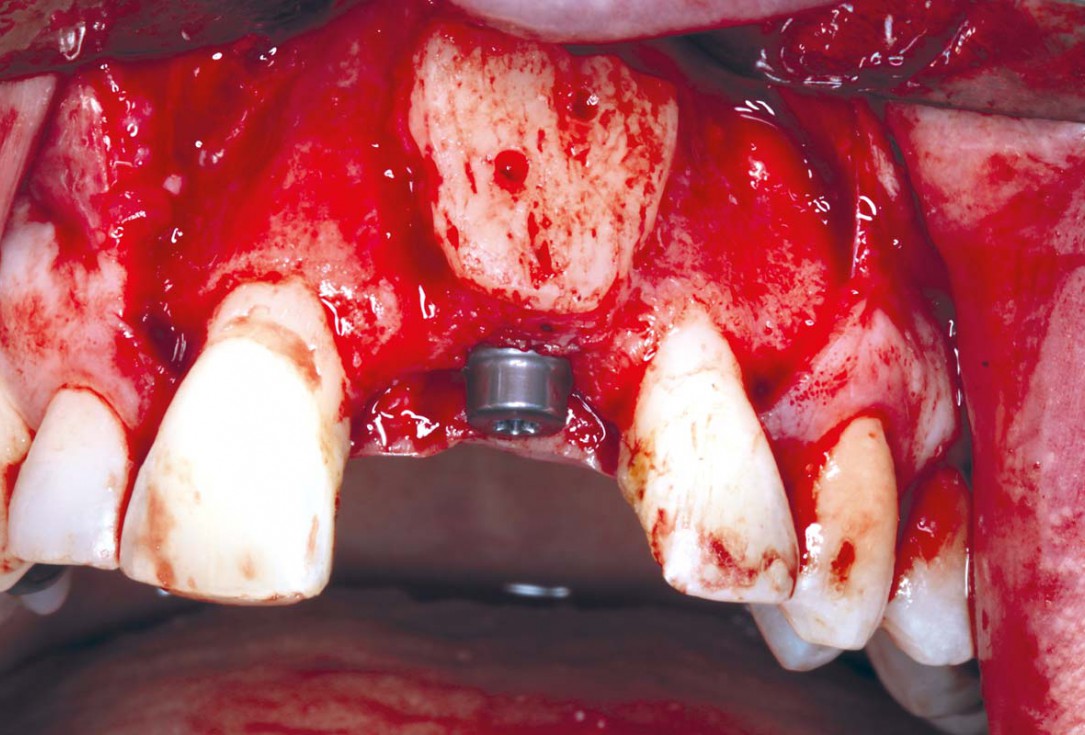

21/35 - Osteotomy prepared revealing a well integrated and nourished bone block. Prostheticly driven implant placement (Straumann Roxolid BLT - RC 4.1x 10 mm) - using a pre-fabricated surgical guide of the approved wax upBlock grafting in the aesthetic zone with maxgraft®, Jason® membrane and cerabone® - Dres. H. Maghaireh and V. Ivancheva

22/35 - Osteotomy prepared revealing a well integrated and nourished bone blockBlock grafting in the aesthetic zone with maxgraft®, Jason® membrane and cerabone® - Dres. H. Maghaireh and V. Ivancheva

23/35 - Implant is placed 3 mm away from the cementoenamel junction. Good primary stability was achieved with a torque of 35 Nom at placement and good block integrationBlock grafting in the aesthetic zone with maxgraft®, Jason® membrane and cerabone® - Dres. H. Maghaireh and V. Ivancheva